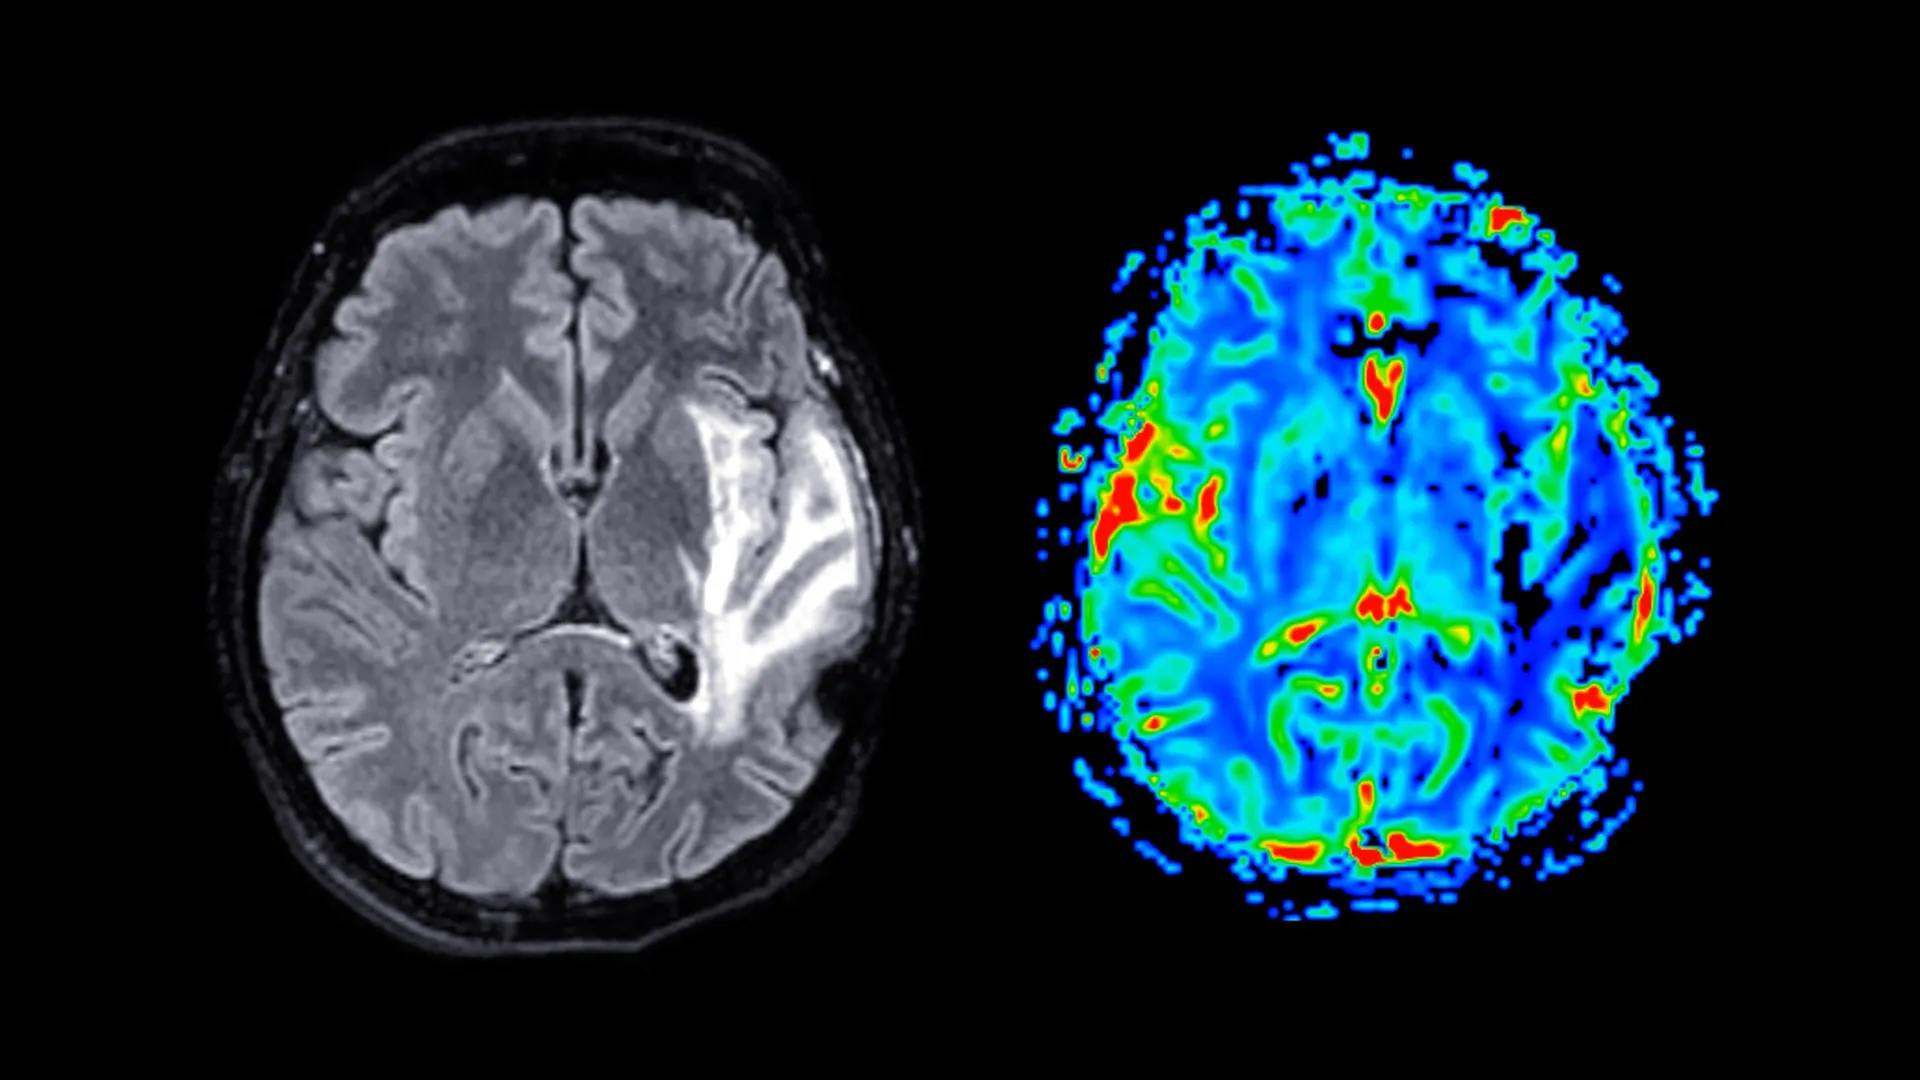

A significant body of scientific inquiry has illuminated a potent connection between specific physiological states and the subsequent development of neurodegenerative conditions, with recent findings pointing towards obesity and hypertension as not merely correlated but direct causative agents in the onset of dementia. This groundbreaking research, detailed in the esteemed Journal of Clinical Endocrinology & Metabolism, shifts the paradigm from association to causality, presenting a compelling case for proactive management of weight and blood pressure as critical pillars of cognitive preservation. Dementia, a complex and escalating global health challenge, currently lacks a definitive cure, leaving millions worldwide to grapple with a progressive deterioration of mental faculties. This decline affects essential cognitive functions such as memory recall, abstract reasoning, and the capacity for problem-solving, fundamentally altering an individual’s ability to navigate daily life. The condition encompasses a spectrum of neurological disorders, with Alzheimer’s disease, vascular dementia, and mixed dementia representing the most prevalent forms. These conditions are characterized by the insidious damage to neural pathways within the brain, leading to a worsening of symptoms over time, impacting language, behavior, and overall cognitive performance.

Further analysis within the study spotlighted the critical role of blood pressure, revealing that a substantial portion of the increased dementia risk associated with obesity is mediated by the presence of hypertension. This significant finding strongly suggests that a dual strategy focused on preventing or effectively managing both obesity and high blood pressure could substantially reduce the likelihood of individuals experiencing cognitive decline later in life. Professor Frikke-Schmidt reiterated the profound implications of these findings, emphasizing that excessive body weight and elevated blood pressure should not be viewed merely as symptomatic indicators but as direct drivers of dementia pathology, thereby positioning them as highly actionable targets for preventative interventions.

The implications for early intervention strategies are particularly compelling, with researchers highlighting the critical timing of therapeutic interventions. While weight-loss medications have been explored in individuals already exhibiting early signs of Alzheimer’s disease, these treatments have not demonstrated a capacity to halt or reverse cognitive decline once symptoms have manifested. However, the study’s findings strongly imply that initiating such interventions prior to the onset of cognitive symptoms could prove profoundly protective. The crucial question that remains is whether therapeutic agents designed to promote weight loss, administered before the insidious development of cognitive impairment, could serve as a prophylactic measure against dementia. The current data strongly supports the hypothesis that early-stage weight-loss interventions are likely to prevent dementia, with a particular emphasis on mitigating the risk of vascular-related dementia, which is intricately linked to the health of blood vessels in the brain.